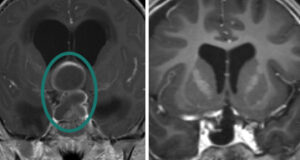

Craniopharyngiomas are typically diagnosed on MRI or CT scan, and are usually distinguishable from the more common pituitary adenomas, Rathke’s cleft cysts and meningiomas that might occur in the region around the pituitary gland and skull base. Craniopharyngiomas typically have both solid and cystic (fluid-filled) components, and many have calcification as seen on CT scan. Complete pituitary hormonal testing is also essential given that a majority of patients will have hormonal deficits. Similarly, most patients will need formal visual field and acuity testing to assess the impact of the tumor on vision and eye movements.

First-line treatment for craniopharyngiomas is maximal safe surgical removal, although in a minority of mostly cystic craniopharyngiomas, simple cyst drainage may be the first treatment. Second-line treatment is typically focused radiotherapy or radiosurgery. Given that most craniopharyngiomas arise along the pituitary stalk, the most common surgical approach is the endoscopic endonasal route via the nostrils. If pituitary gland function is intact, every attempt is made to preserve the integrity of the pituitary gland and stalk and its connection to the hypothalamus. Alternatively, for tumors that extend far off the midline and for some recurrent craniopharyngiomas, a supraorbital “eyebrow” craniotomy can be used. Several examples of these approaches for craniopharyngioma are shown in our video library.